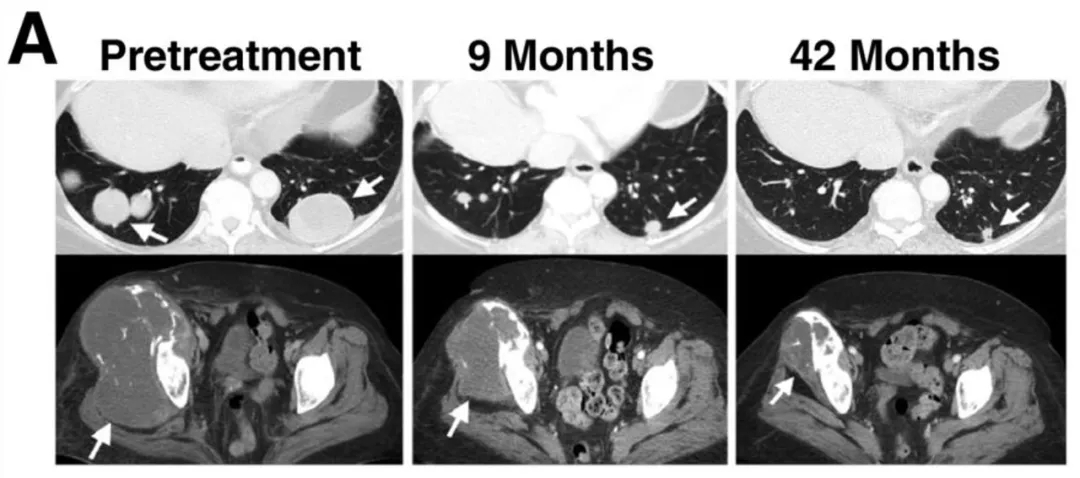

在滑膜肉瘤患者中,除2号患者外,其余缓解患者均在首次接受1G4-αLYTCR治疗后出现疗效。该组患者部分缓解持续时间为3~18个月,3年和5年总生存率估计值分别为38%、14%(详见下图A)。2号患者首次输注后获6个月部分缓解,二次输注同类T细胞产品后再次实现9个月部分缓解,总缓解持续时间达18个月。该组中有2例患者实现长期持续缓解:

7号患者肺部多发转移灶近乎完全消退,盆腔大骨病灶显著缩小,疗效维持近4年(详见下图A)。